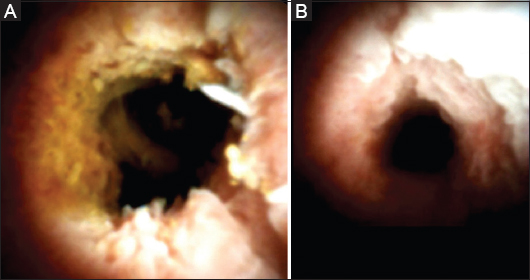

The patient was admitted 6 months later, having undergone cholecystectomy, in order to undergo repeat ERCP for stent removal. In the meantime, he remained asymptomatic. Besides the known stricture, a hilar hepatic stricture was also demonstrated during the ERCP procedure. Cholangioscopy (SpyGlass, Boston Scientific, Marlborough, USA) revealed an irregular pattern, mucosal friability and anarchic vascularization (Fig. 1; Video 1) while targeted biopsies from the strictures showed non-specific signs of chronic inflammation. A new MRCP scan confirmed the ERCP findings (Fig. 2). Quantification of serum immunoglobulins showed normal levels of IgG4 (76.9 mg/dL, NR 8-140). Viral serology, cancer antigen 19-9, α-fetoprotein, carcinoembryonic antigen, anti-nuclear antibodies, antineutrophil cytoplasmic antibodies, anti-smooth muscle antibodies, and anti-mitochondrial antibodies were all negative.

Figure 1 Cholangioscopic view of the (A) hilar hepatic stricture, and (B) common bile duct stricture, showing an irregular pattern, mucosal friability and anarchic vascularization (SpyGlass, Boston Scientific)